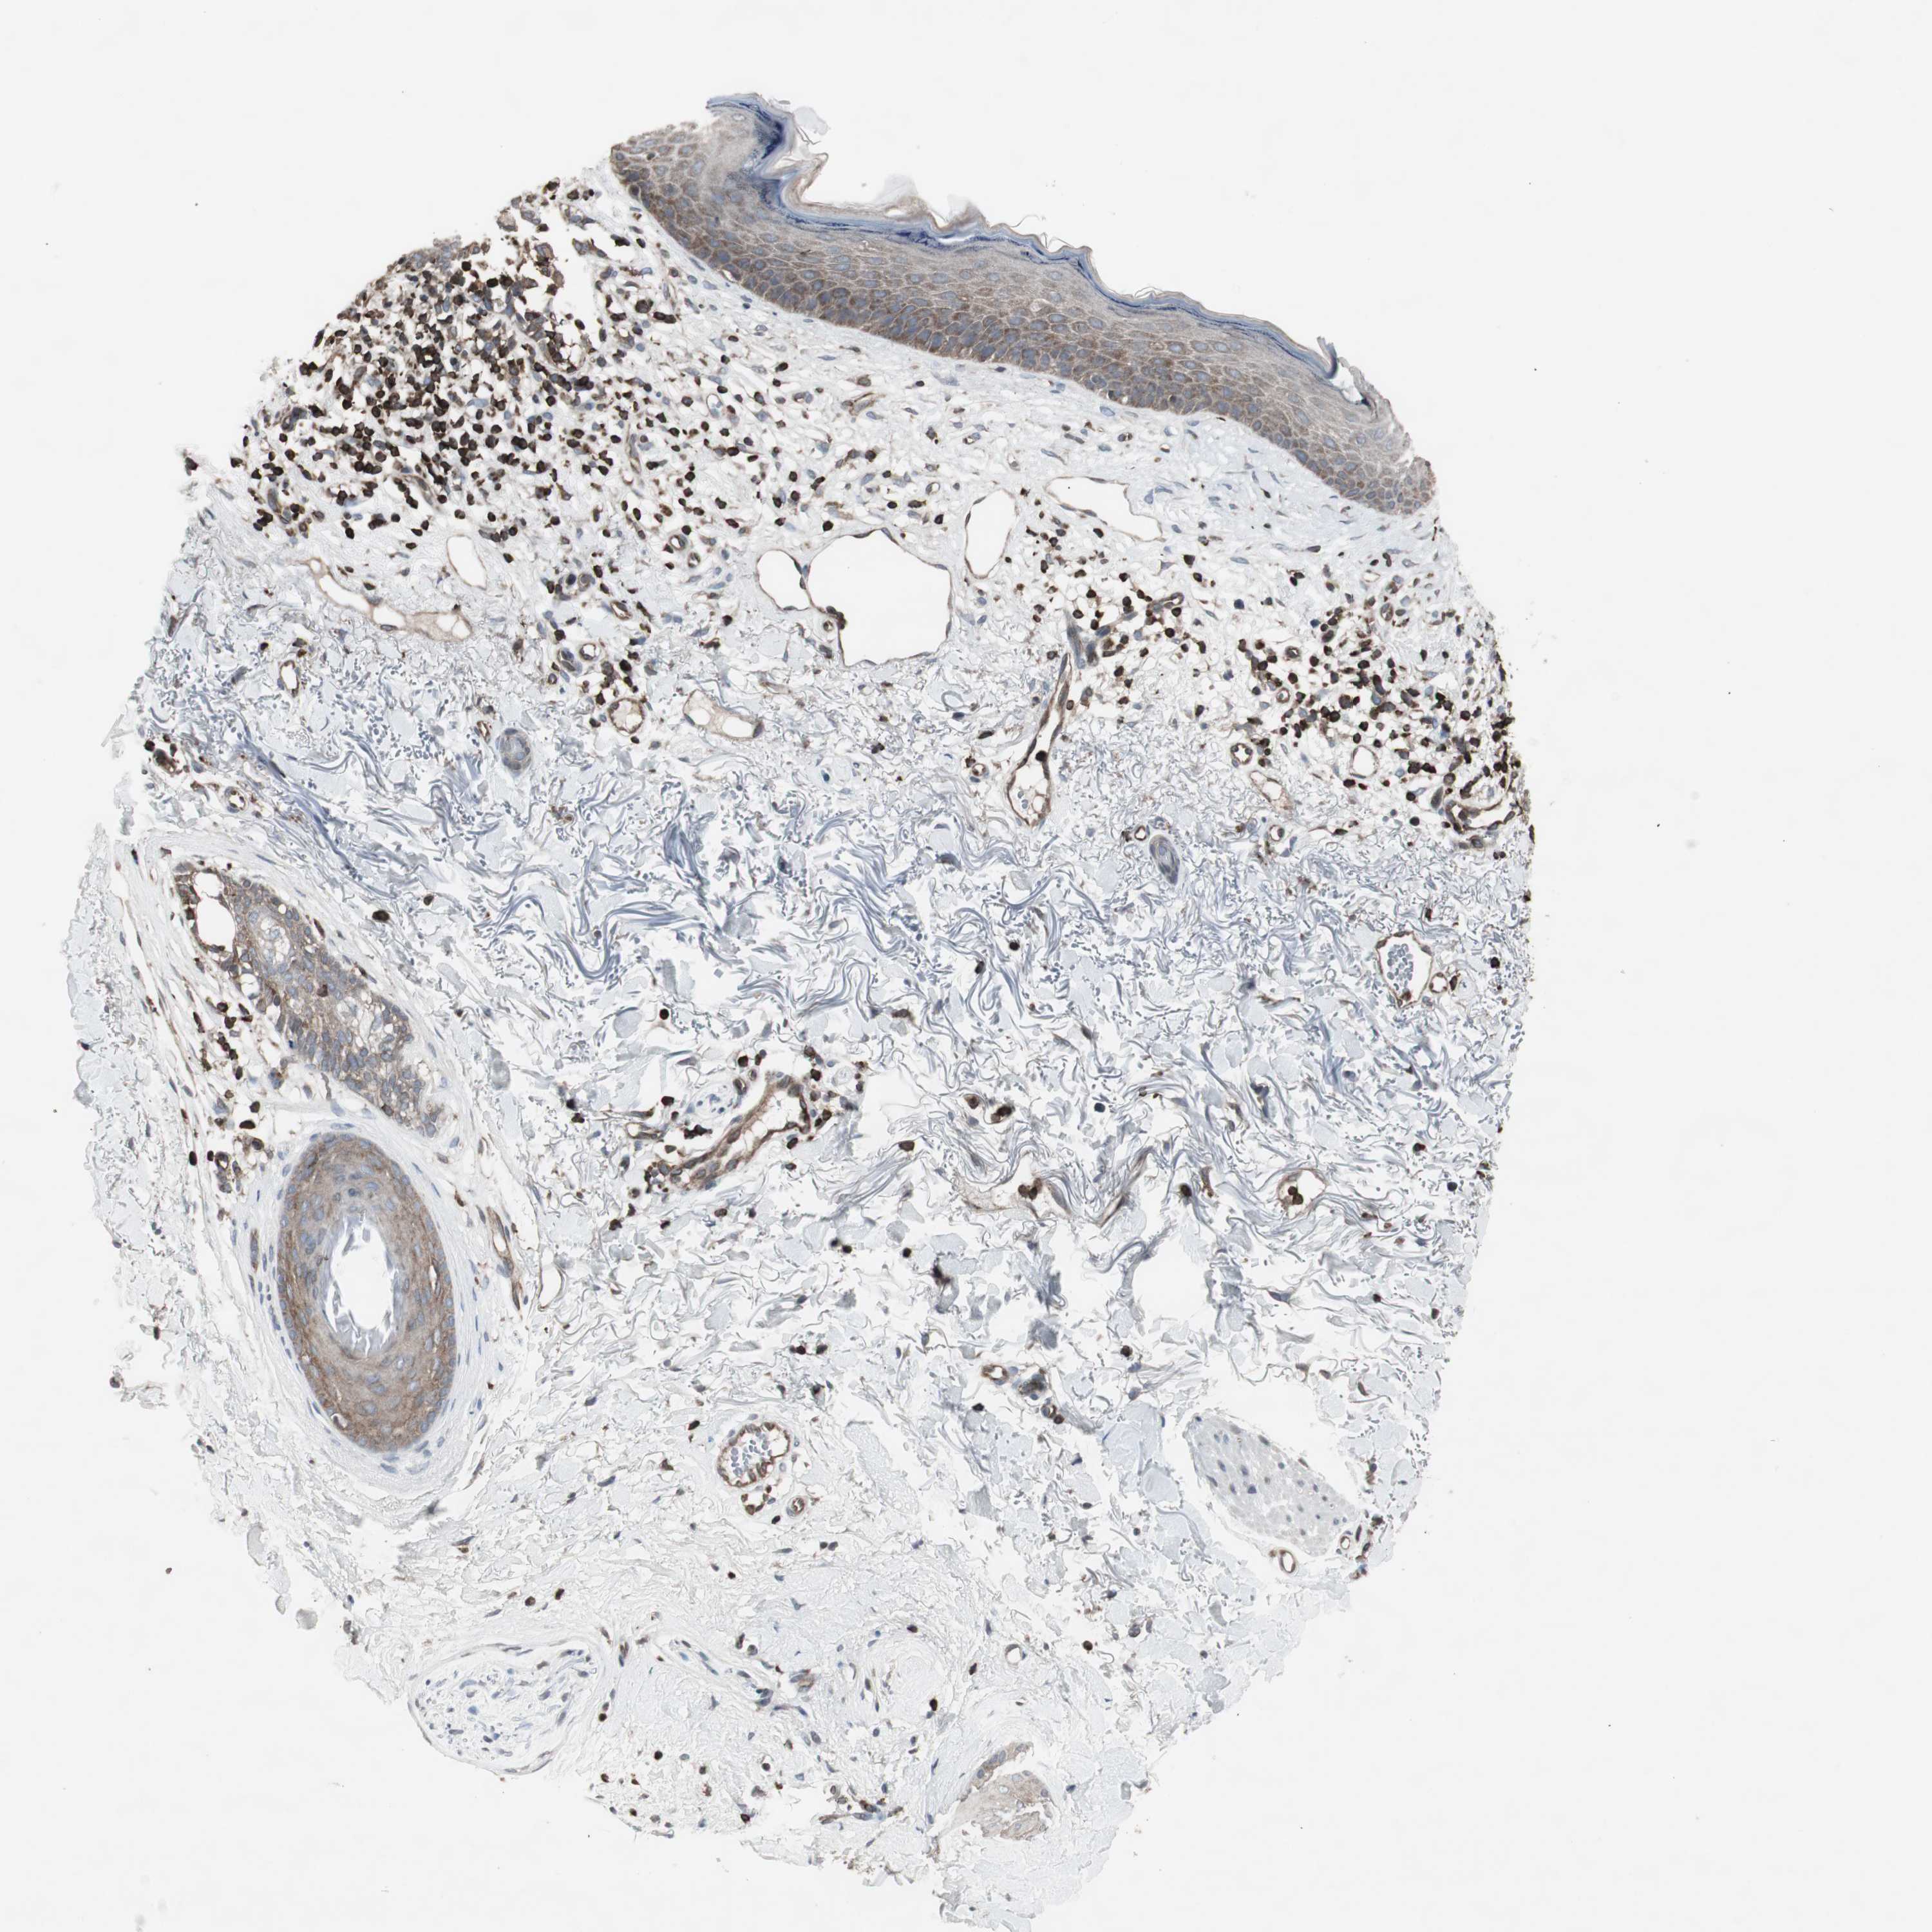

Basal cell and squamous cell cancer

SKIN CANCER - Protein expressioni

A mouse-over function shows sample information and annotation data. Click on an image to view it in a full screen mode. Samples can be filtered based on level of antibody staining by selecting one or several of the following categories: high, medium, low and not detected. The assay and annotation is described here.

Each image is clickable and will lead to virtual microscopy that enables deeper exploration of all samples and also displays staining intensity scores, fraction scores and subcellular localization as well as patient and tissue information for each sample.

Antibody CAB009502

Basal cell carcinoma